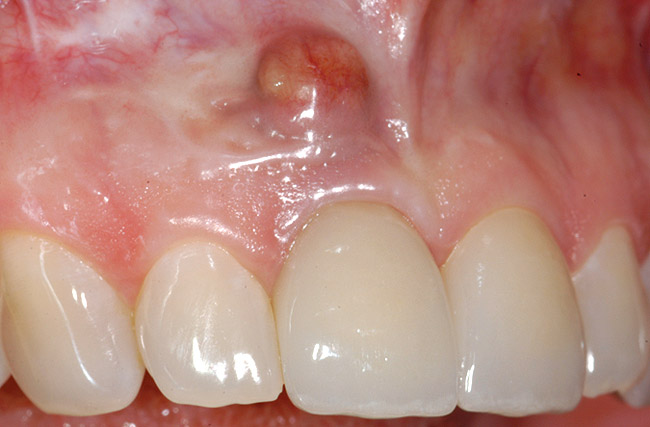

A 39-year-old woman presented with a failing endodontically treated maxillary right central incisor. Clinical and radiographic examination revealed a thick, flat periodontal biotype, high smile line, and a fistulous tract of the labial vestibule opposite the incisor (Figure 16 and Figure 17). Also noted post-extraction was a thin (< 2 mm) labial plate with 8 mm of vertical bone loss (Figure 18). Treatment consisted of a conservative flapless extraction with placement of a free connective tissue graft (Figure 19) sutured through the socket, along with placement of a bone mineralized allograft (MinerOss) (Figure 20 and Figure 21). Five months post-extraction, a root-form implant was placed, nonsubmerged, along with a bovine bone xenograft as a veneer into a sub-periosteal labial pouch (Figure 22 through Figure 24). A provisional crown was placed 3 months later, allowing for adequate soft-tissue grooming (Figure 25).

Figure 16  Failing maxillary right central incisor with fistula.

Figure 16

Figure 17  Periapical radiograph indicating periapical pathology and failing root canal.

Figure 17